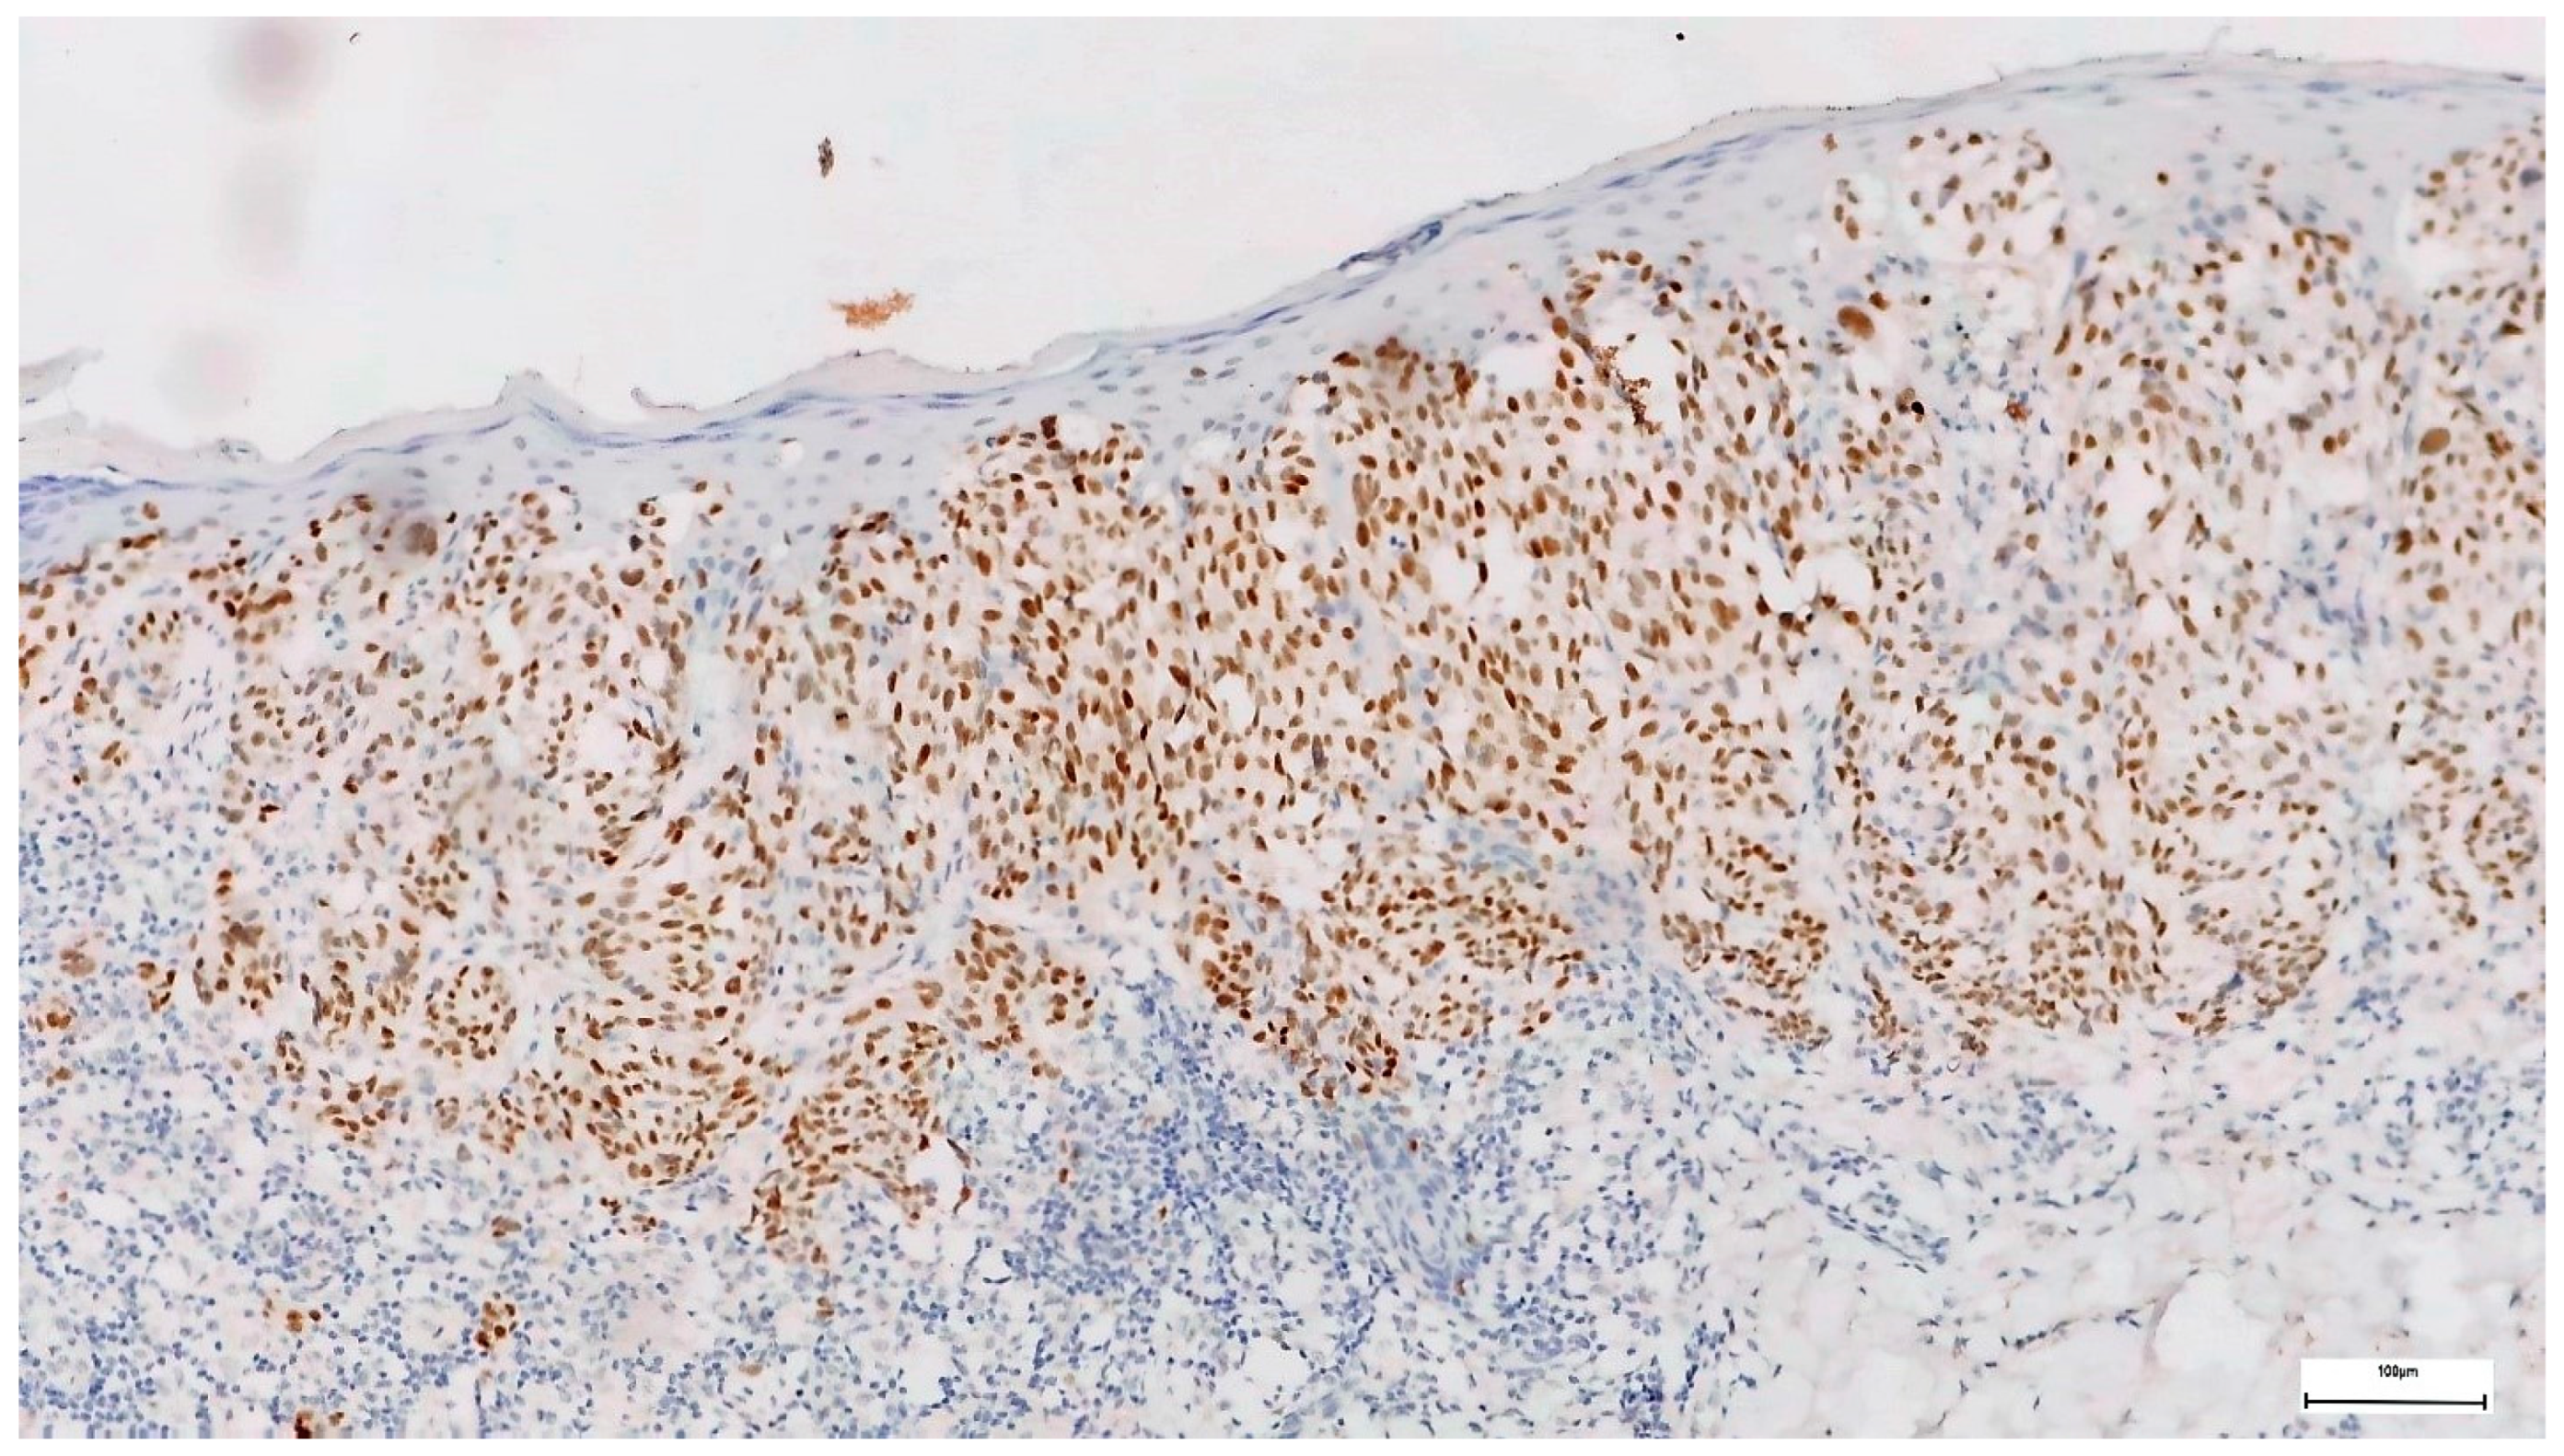

3. Results